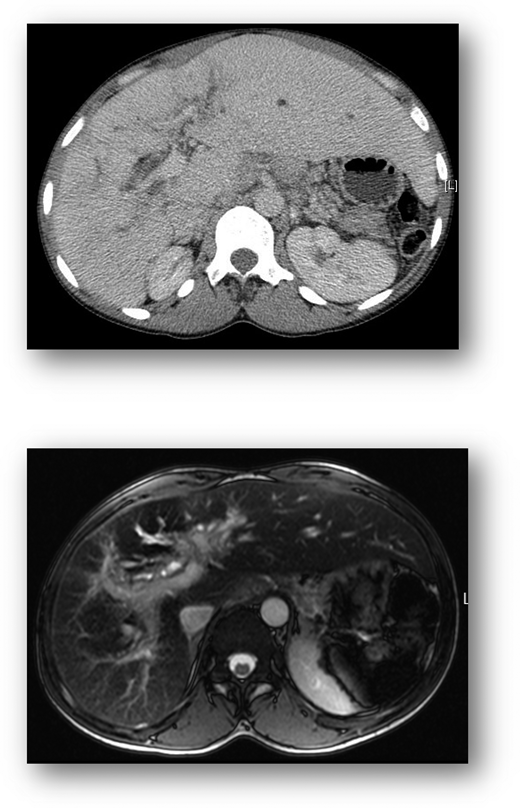

Over the next 4 years, the clinical phenotype was of a progressive predominantly cholestatic abnormality of liver function, punctuated by episodes of acute liver dysfunction similar to that described in the previous paragraphs during sickle crises (Figure 1). Further liver investigations performed included abdominal computed tomography (CT) and liver magnetic resonance imaging (MRI), which demonstrated (Figure 2) hepatomegaly with an irregular liver outline suggesting the development of chronic fibrotic disease, and right and left intrahepatic duct dilatation, suggestive of a cholangiopathy. Laboratory results revealed negative viral serology (for hepatitis B, hepatitis C, and hepatitis E), and a negative liver autoantibody screen (excluding liver autoimmune disease). Ferritin levels in steady state were markedly raised at 3000 to 4000 µg/L. An R2-MRI of the liver showed a liver iron concentration of 7.9 mg Fe/g dry weight consistent with transfusion-related iron overload.

Cross-sectional imaging. CT liver (top) demonstrates hepatomegaly and irregular liver outline suggesting established chronic liver disease. MRI of the liver (bottom) shows diffuse injury of the intrahepatic bile ducts, indicative of an established cholangiopathy

Appropriate imaging studies include abdominal ultrasound, cross-sectional imaging with CT or MRI scan, and indirect cholangiography. The liver is usually enlarged and splenic infarction characteristic. Irregularity of the liver outline is suggestive of established fibrotic disease. Magnetic resonance cholangiography will identify cholelithiasis and choledocholithiasis as well as cholangiopathic change.10